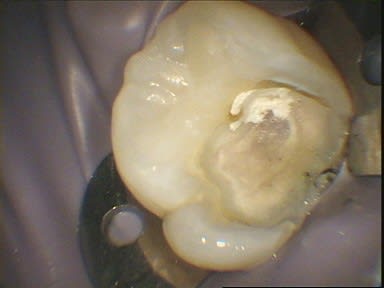

Par comparaison, quelques photos de coiffage pulpaire au CO²